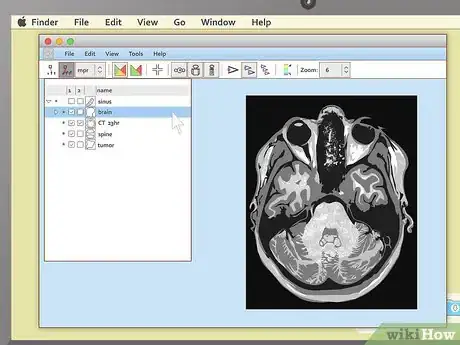

4Load the study. Again, the exact steps you'll need to take here can vary slightly depending on the exact program you have packaged with your images. Generally, most MRI viewers will have some sort of option to load or import images that you can select from the menu bar at the top of the screen. In this case, select this option, then pick the image file on your disc that you'd like to look at.

- Note that most medical imaging software refers to collections of images as "studies". You may not see an "import image" option, but you'll probably see something to the effect of "import study."

- Another option you may encounter is that, as soon as the program loads, it will present you with a "table of contents" of all the MRIs on the disc. In this case, simply select the study you want to view first to proceed.

5View the images. Most MRI programs start with a large black space on one side of the screen and a smaller toolbar on the other side. If you see small preview pictures of your MRI images in the toolbar, double click on the image you want to view. It should load a large version of the image into the black area.

3Use cross-sectional views to spot abnormalities in brain MRIs. MRIs of the brain tissue are often used to check for brain tumors, abscesses, and other serious problems that can affect the brain. The easiest way to see these things is usually to choose the cross-sectional view, then descend slowly from the top of the head downward. You're looking for anything that's not symmetrical — a dark or light patch that's on one side but not the other is cause for concern.

- Brain tumors often take the form of round, golf ball-like growths in the brain which will usually show up as either bright white or dull grey surrounded by a ring of white. However, other brain problems (like multiple scleroses) can also have a whitish appearance, so this alone may not be a sign of a brain tumor.